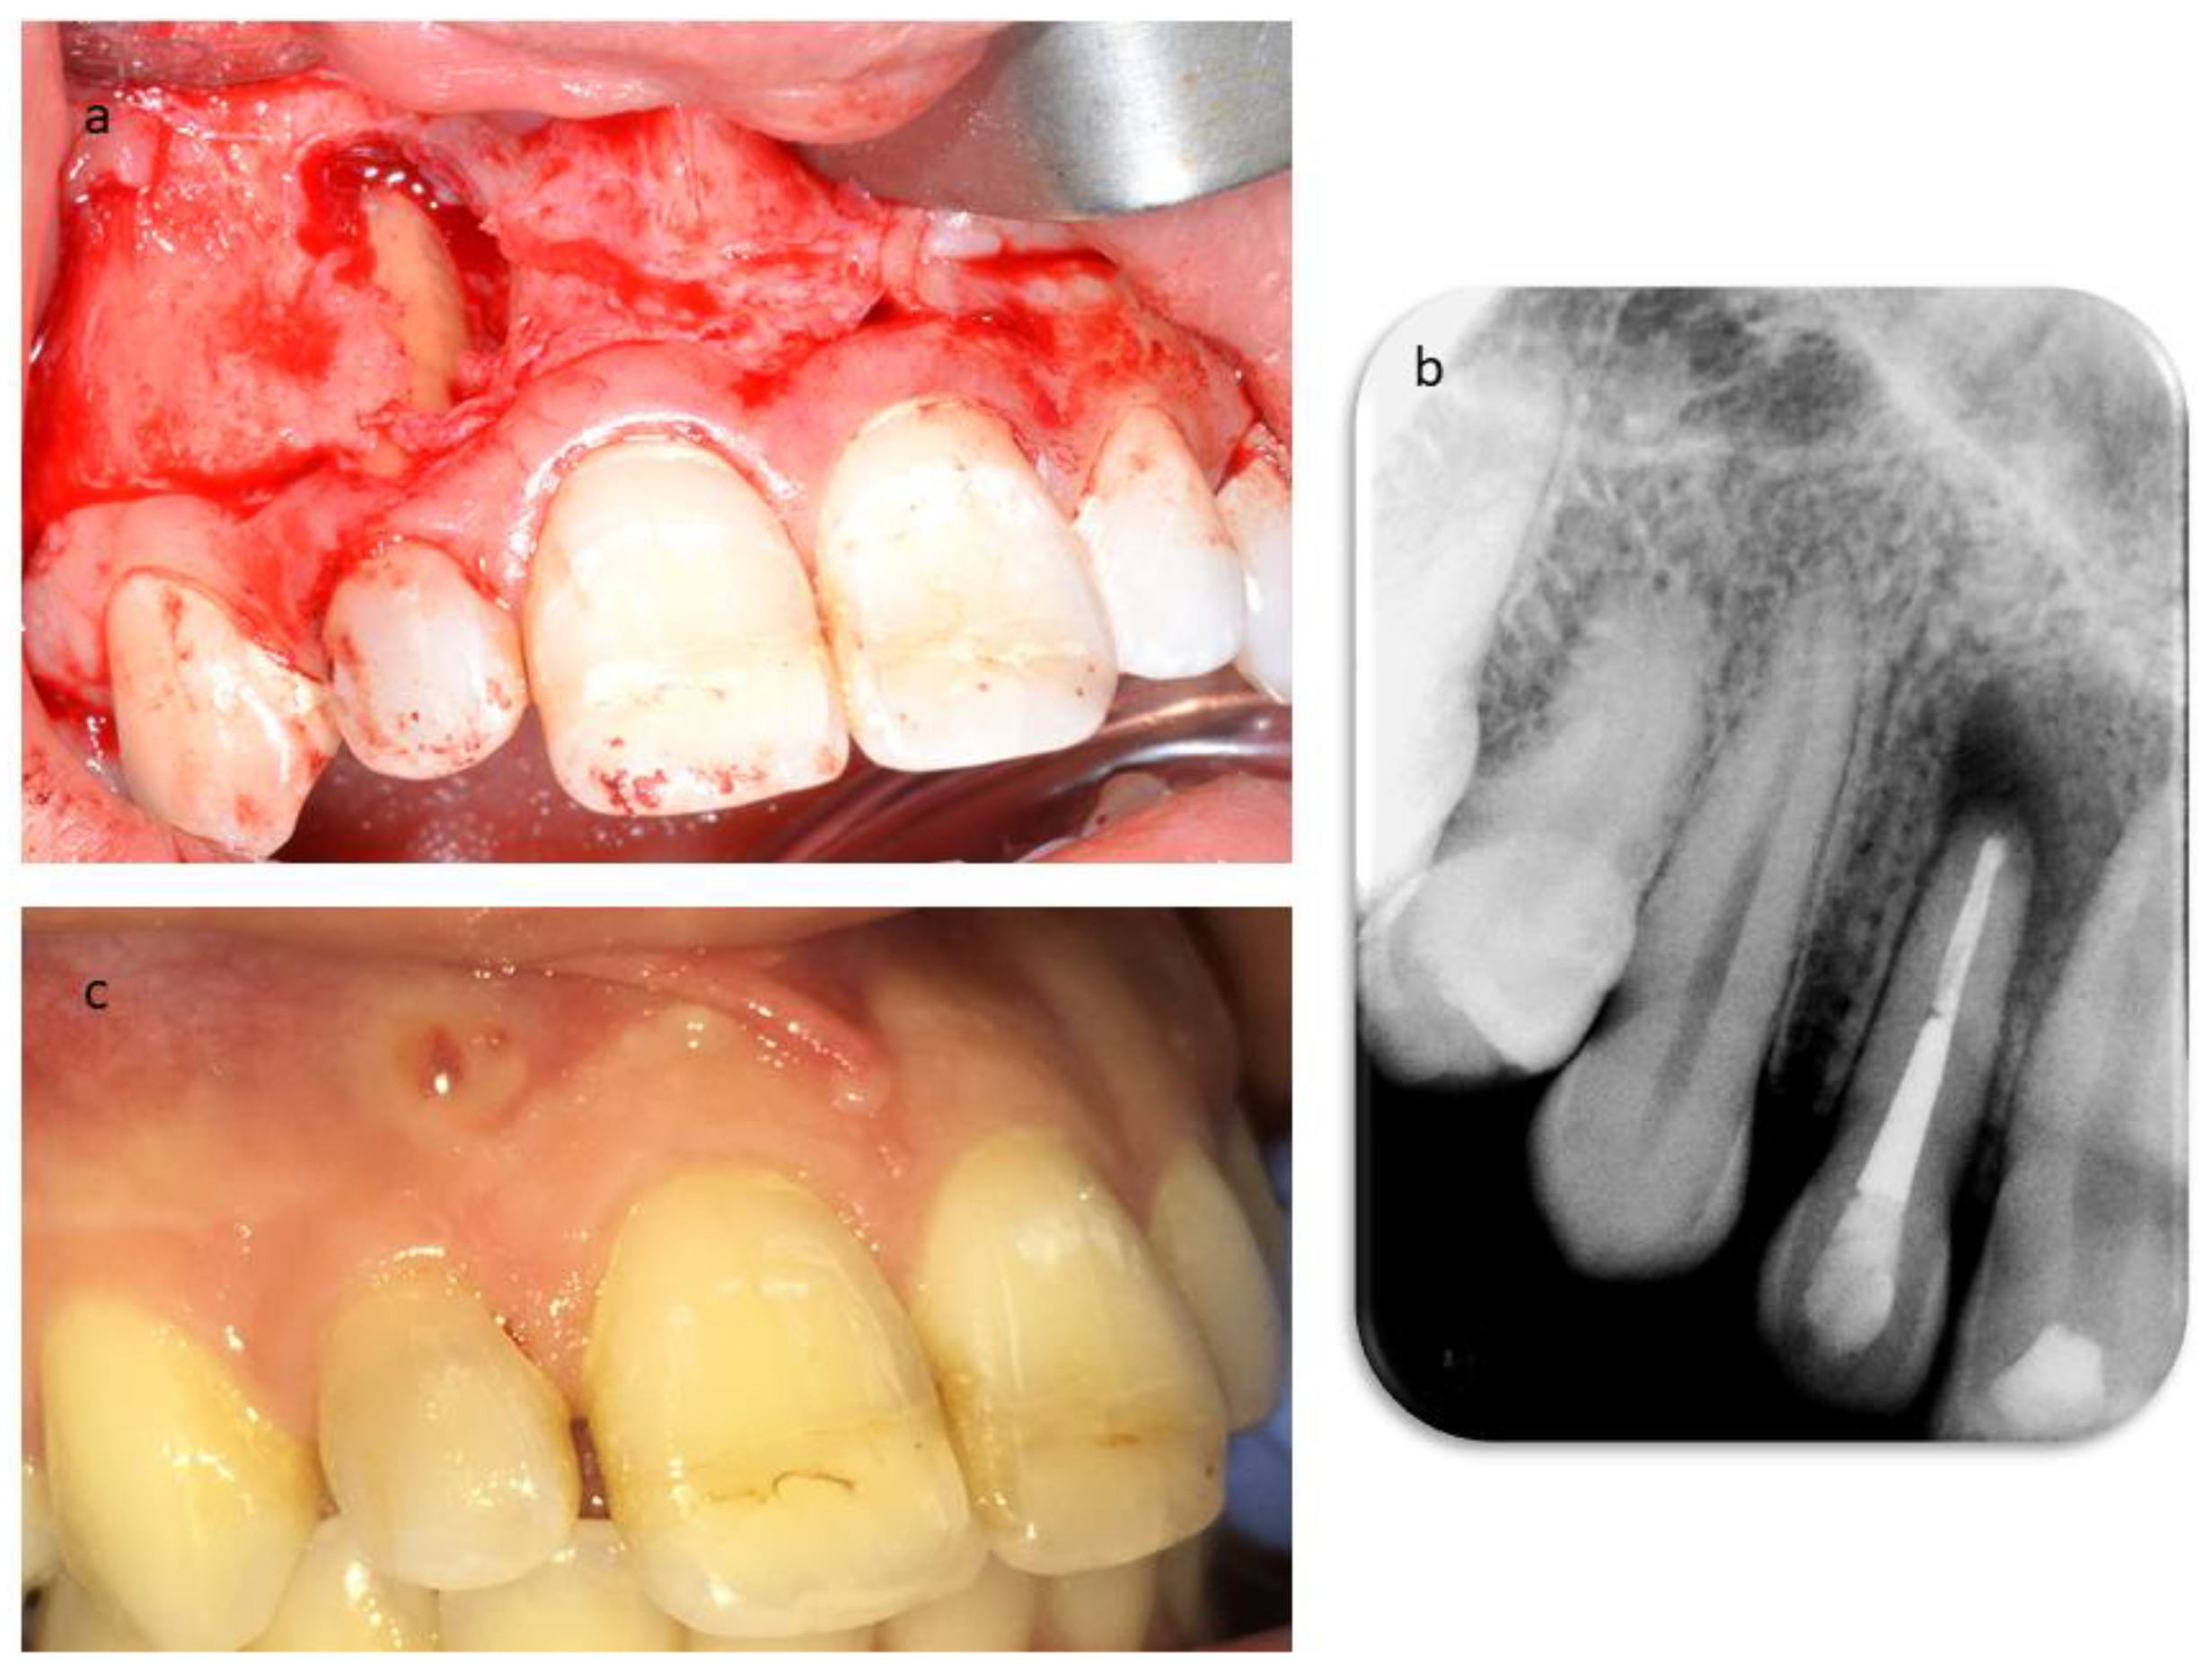

2. Case Report